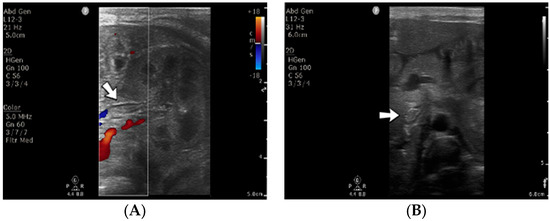

A 3-day-old male neonate (38 weeks, 3 kg) presented with sepsis and acute renal failure, which developed at 48 h of life. The laboratory findings from birth showed mild thrombocytopenia and elevated c-reactive protein. On admission, normal coagulation tests and D-dimer tests were detected. An abdominal ultrasound revealed thrombosis of the inferior vena cava, both renal veins, and the left common iliac vein (Figure 10). Continuous renal replacement therapy was initiated, with continuous heparin infusion for the hemodialysis device. Treatment with bivalirudin was associated for two days, and then switched to alteplase. The D-dimer values increased to undetectable levels.

Figure 10.

Thrombosis of the left renal vein (A) and thrombosis of the inferior vena cava (B) were noticed on abdominal ultrasound. No Doppler signal was identified on the renal vein versus the renal artery (A).

Even though revascularization of the right renal vein was detected on ultrasound after ten days of continuous infusion with alteplase, anuria persisted. Multiple warnings of filter clotting and high transmembrane pressure through the filter were received, which led to several heparin bolus administrations and multiple replacements of the CRRT circuit. The patient died at 20 days of life due to multiorgan failure.

Genetic testing confirmed inherited thrombophilia, with a positive MTHFR A1298C heterozygous gene mutation and Antithrombin, Protein S, and Protein C deficiencies. A moderate elevation of PAI-1 was also detected. There was a positive family history of maternal thrombophilia, one maternal miscarriage, and an older brother known with perinatal stroke.